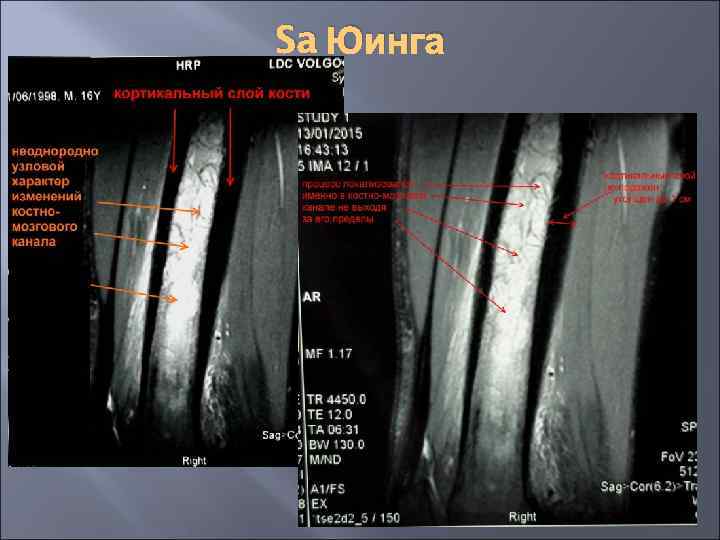

Sa Юинга Юноша, 17 лет: около 3 лет беспокоят периодические боли в ср/3 правого бедра, около 1 года боли имеют ночной характер, около 3 месяцев – принимает ежедневно обезболивающие препараты внутрь, около 1 месяца – на ночь требуется инъекция в/м обезболивающих. Клинически – окружность ср/3 -н/3 правого бедра = 38, 5 см, а окружность ср/3 левого бедра – 37, 5 см, по результатам УЗИ от 15. 01. 15 г – новообразований в мягких тканях ср/3 правого бедра не выявлено. По результатам МРТ от 13. 01. 15 г имеется неоднородная мелкоузловое поражение структуры ткани в костно-мозговом канале ср/3 правой бедренной кости (на расстоянии между 8 см до 18 см считая от верхнего края надколенника). Ro правого бедра от 16. 01. 15 г – на протяжении около 13 см в ср/3 -н/3 правой бедренной кости имеется неоднородная структура костно-мозгового канала, утолщение кортикального слоя до 1 см в ср/3, деструкции – нет, периостальной реакции - нет. Операционная биопсия 27. 01. 15 г сверлом диаметром 2 мм выполнены остеоперфорации на участке 2, 5 х1 см (толщина кортикального слоя до 1 см) – удален участок кортикального слоя 2, 5 х1 см до костно-мозгового канала, в костно-мозговом канале имеется фиброзноподобная опухолевая ткань вперемешку с тканью костного мозга – ложкой Фолькмана произведен забор содержимого костномозгового канала на участке до 5 см (вверх и вниз от перфорационного отверстия). Цитологическое исследование мазков отпечатков с содержимого костно-мозгового канала от 30. 01. 15 г: клетки злокачественного новообразования – возможно Sa Юинга. Гистологическое исследование № 1935 - 40 от 30. 01. 15 г – злокачественная недифференцированная опухоль с выраженным сосудистым компонентом

Sa Юинга